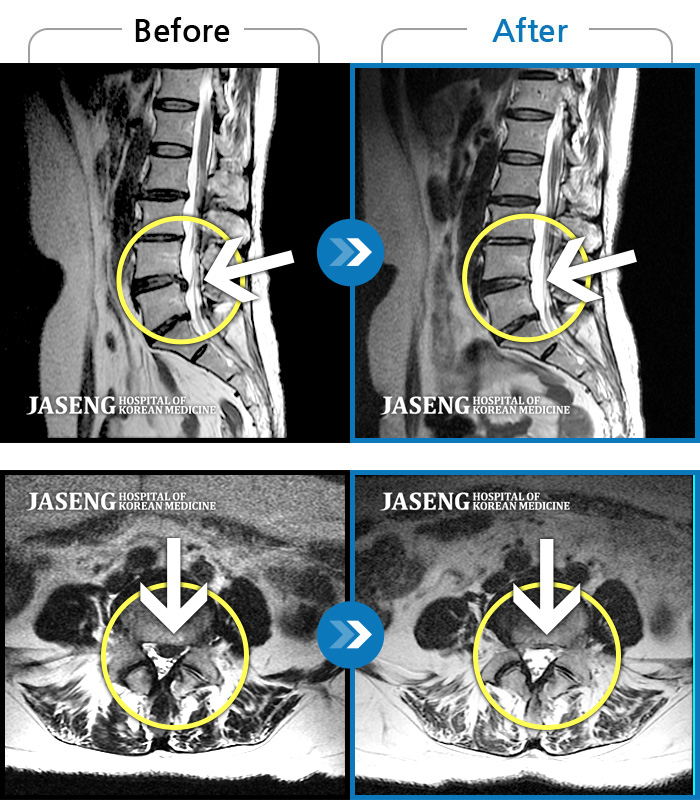

허리디스크

안산 · 김민수 원장

허리가 아프고 두 다리가 저려서 조금만 걸어도 주저 앉아야 했습니다.

촬영시기

2018.12.20 ~ 2023.02.21

2023.02.24